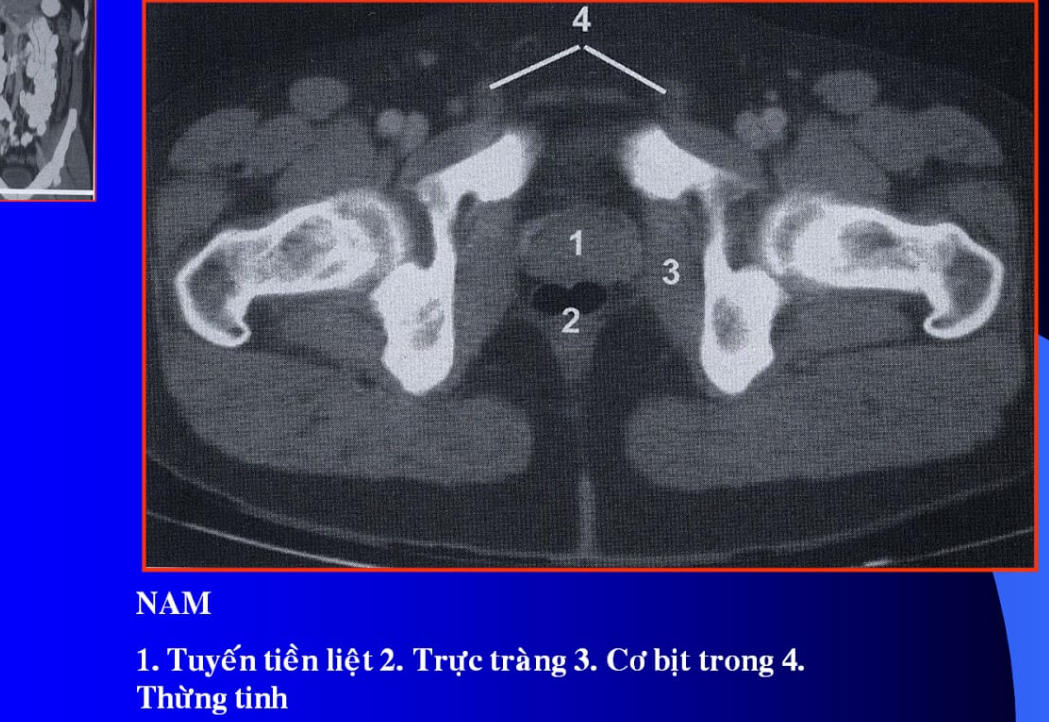

cq trong hình ?